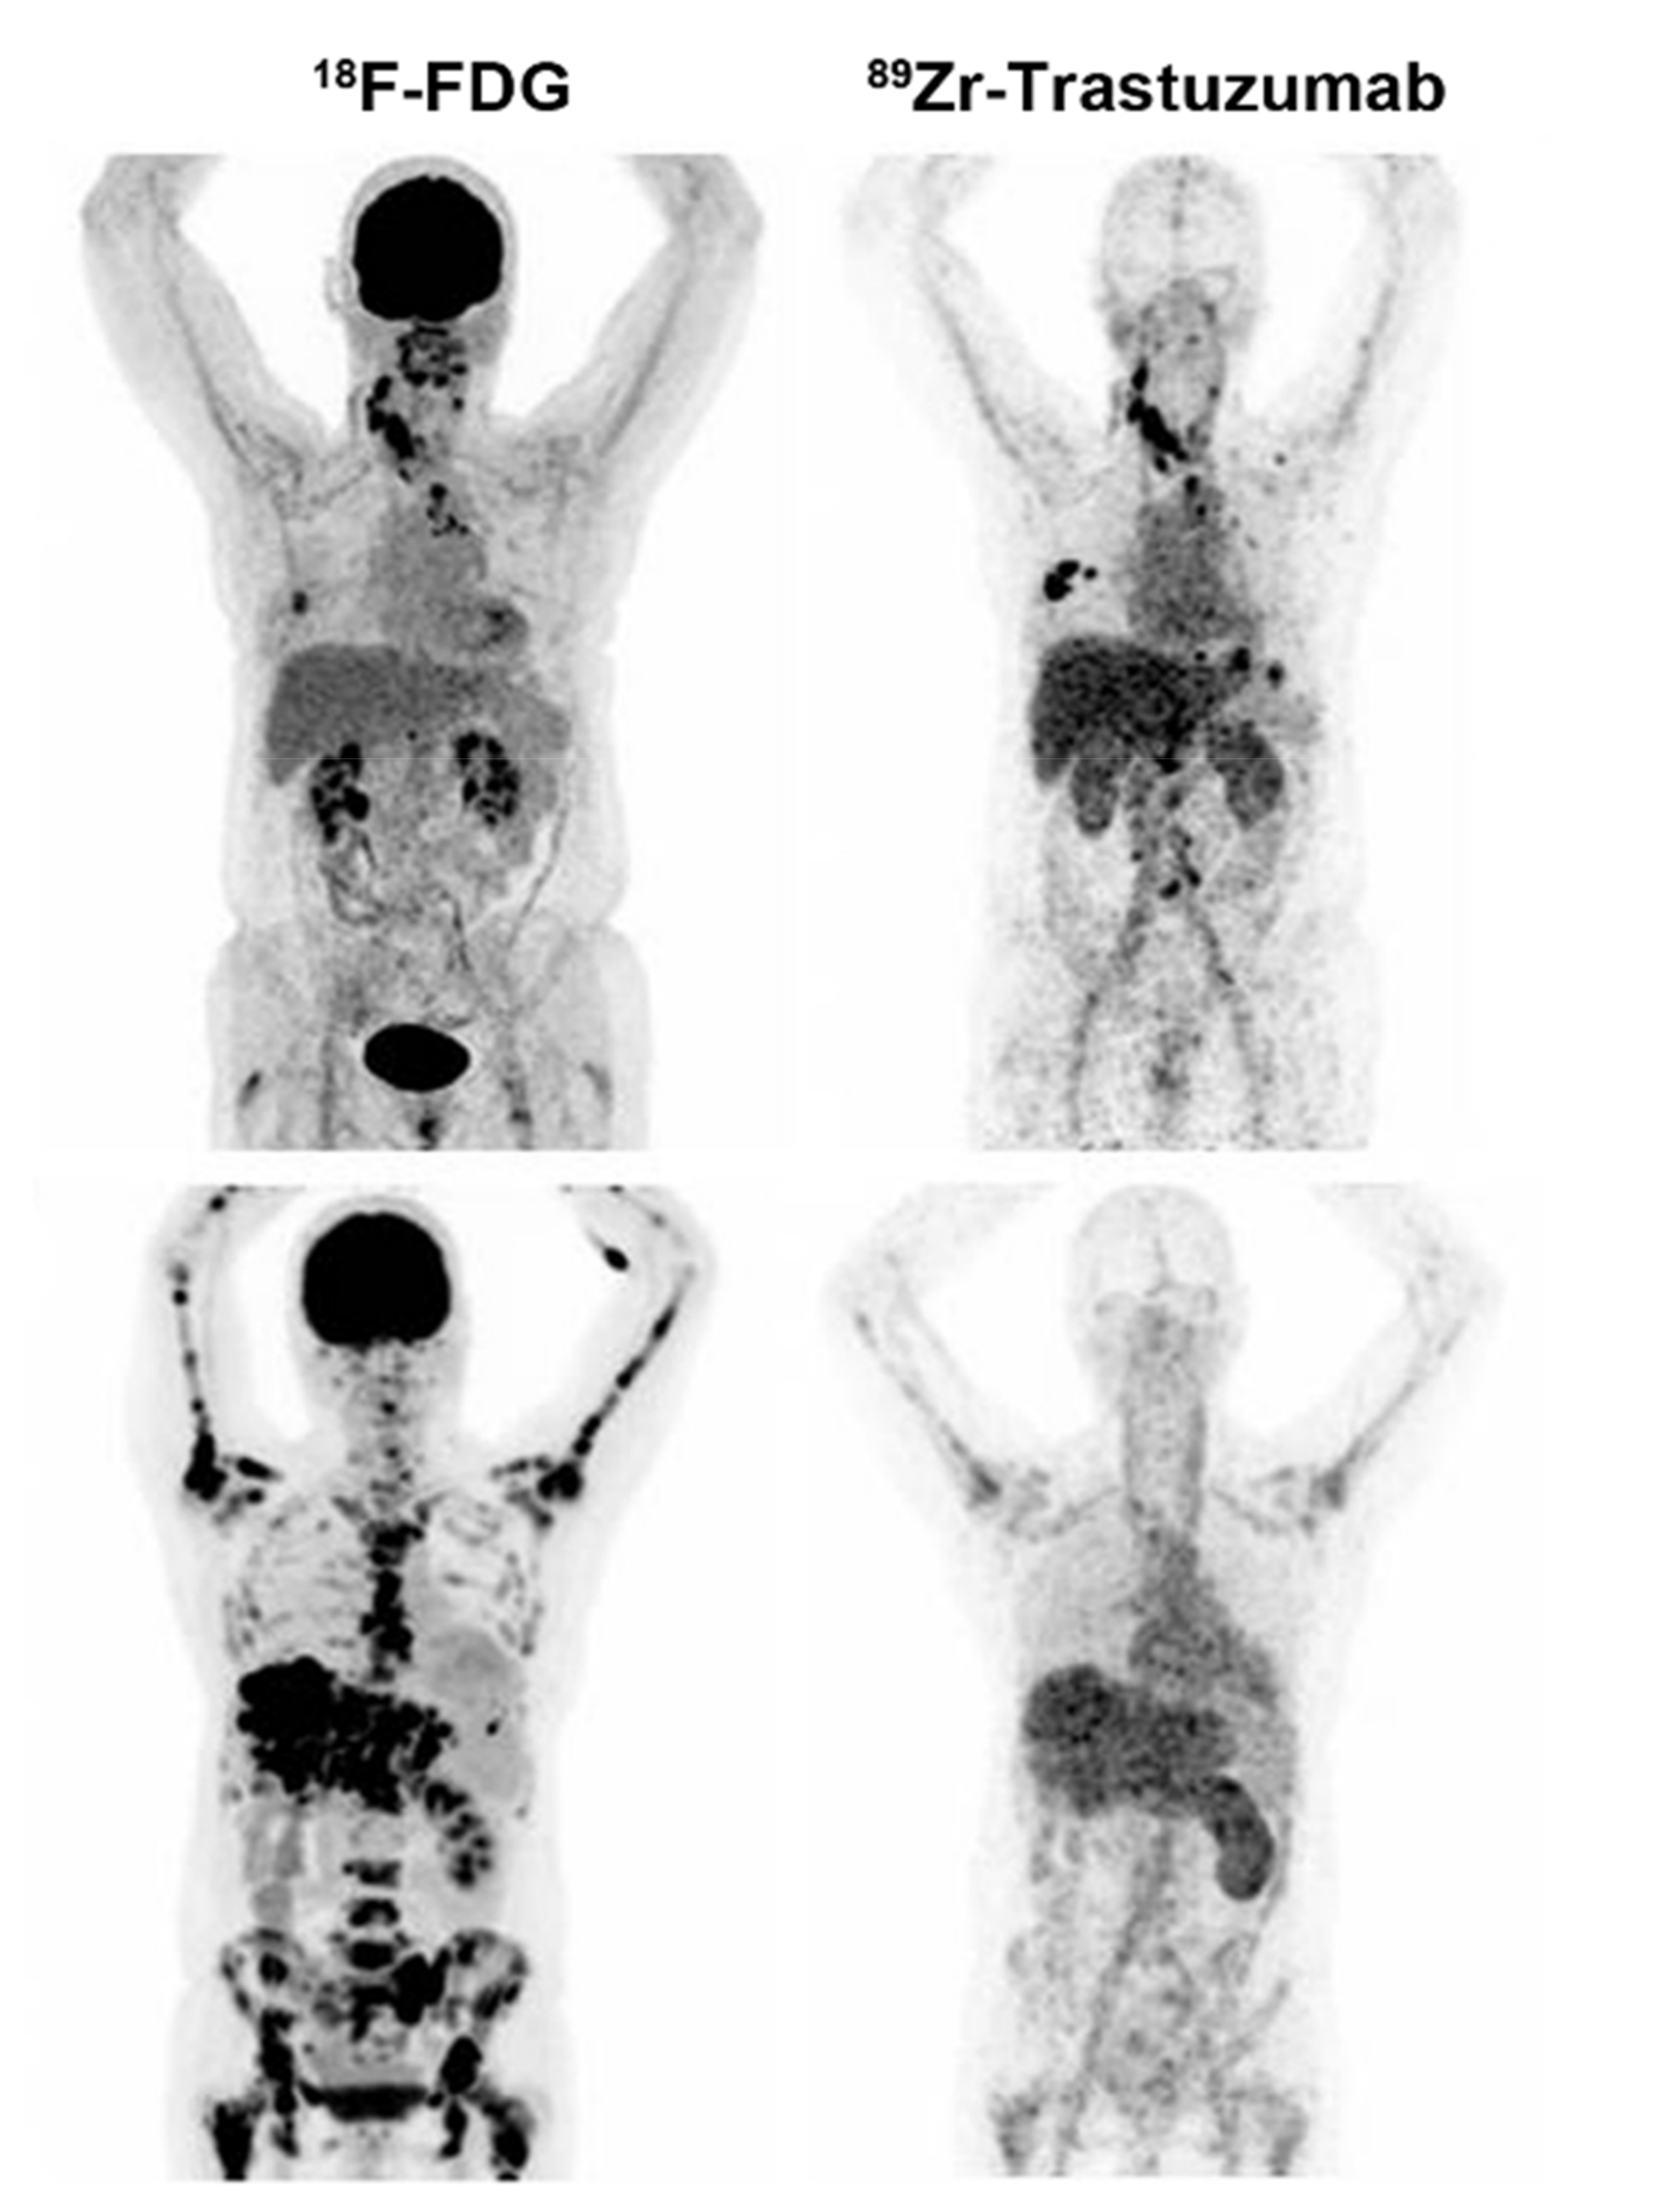

| PET | CXCR4 antagonist | 64Cu-AuNCs-AMD3100 (targeting CXCR4) | 1. Flexible and straightforward preparation 2. High radiolabeling specific activity 3. Sensitive and accurate detection of CXCR4 | The ability to determine tumor progression and burden needs further improvement | [20] | ||

- Zhao, Y.; Detering, L.; Sultan, D.; Cooper, M.L.; You, M.; Cho, S.; Meier, S.L.; Luehmann, H.; Sun, G.; Rettig, M.; et al. Gold Nanoclusters Doped with (64)Cu for CXCR4 Positron Emission Tomography Imaging of Breast Cancer and Metastasis. ACS Nano 2016, 10, 5959–5970. [Google Scholar] [CrossRef]